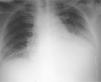

Pericarditis purulenta como complicación de la neumonía neumocócica bacteriémica